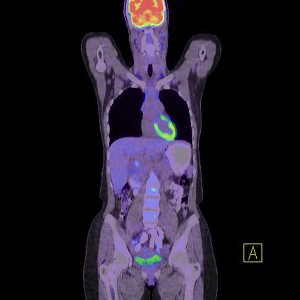

A PET/CT (pozitronemissziós tomográf és egy CT kamera egy készülékben) vizsgálatok nem csak azok számára adnak választ, akik valamilyen rákos megbetegedéssel érkeznek hozzánk, hanem azok számára is, akik szeretnének meggyőződni arról, hogy szervezetükben nincs jelen semmilyen daganat.

A vizsgálat során a szervezetbe intravénásan egy FDG nevű anyagot adunk, (ez egy szőlőcukor molekulához kapcsolt fluor izotóp) amely azután szétterjed a szervezetben, hiszen a sejtek működésük során cukrot használnak fel. A vizsgálati képeken látható színes foltok jelölik azokat a gócpontokat, ahol ez az anyag felhalmozódik, ugyanis a daganatok sokkal több cukrot használnak fel működésük során, ezáltal a fluor is felhalmozódik és a PET kamera ezt érzékeli.

A CT képekre rávetített PET felvételek segítségével nagyon pontosan lokalizálható az elváltozás, valamint annak pontos mérete is meghatározható. A PET/CT akár már 2-3 mm-es állapotában felfedi a daganatos elváltozásokat, ami azért fontos, mert a korai stádiumban a rák nagyon jó eséllyel gyógyítható, ha időben megkezdik a megfelelő kezelést.